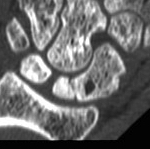

CT

Increased sclerosis of the proximal pole

Fragmentation and collapse of the proximal pole